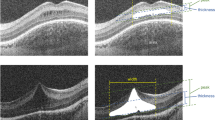

To determine the prevalence of cystic macular oedema (CME) in patients with choroideremia (CHM) by using spectral-domain optical coherence tomography (SD-OCT).

A total 16 patients affected with CHM were enroled in the study. All patients underwent a complete eye examination. SD-OCT was performed using an OPKO spectral-domain OCT/SLO instrument.

The average age of the study patients was 44.0±16.0 years (range, 13–63 years). Out of the 16 patients with CHM, 10 patients (62.5%) showed a degree of CME on SD-OCT testing in at least one eye, and 8 patients (50%) showed CME in both eyes.

Because of its notable prevalence, it would seem prudent to screen CHM patients by SD-OCT for the possible presence of CME and to identify those amenable to future treatment strategies for their macular oedema.